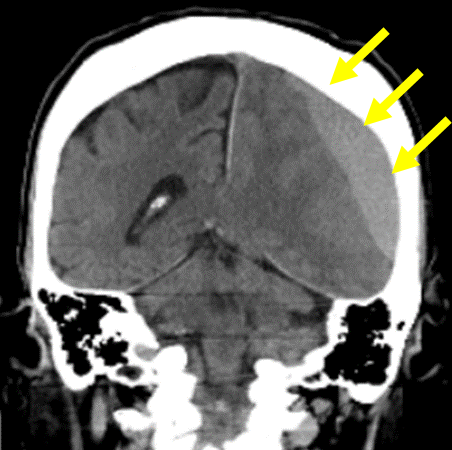

先ほど示した症例の経過観察後のMRI画像

血腫の量が少ない&症状が軽微の場合は外来通院治療でも治癒することが多い

急性硬膜下血腫と異なり、じわじわと血液が滲み出してくる慢性硬膜下血腫は、安静に過ごすことでまた自然と吸収してくれることがあります。

血腫の量が少なく、かつ症状が軽い場合は、経過観察の方針となります。通常、以下のように指導を行います。

一カ月前に転倒し頭部打撲。転倒当日CT検査を行い異常なし。転倒から一カ月後から返答がうわのそら、さらに歩行時のふらつきが目立つようになり受診

→に血腫を認める。血腫による圧迫により健常側に見られる脳のしわ(→)が潰れている。

→に厚い血腫を認める

穿頭(せんとう)血腫除去術後

血腫は除去されている

術後から症状は改善され、退院。